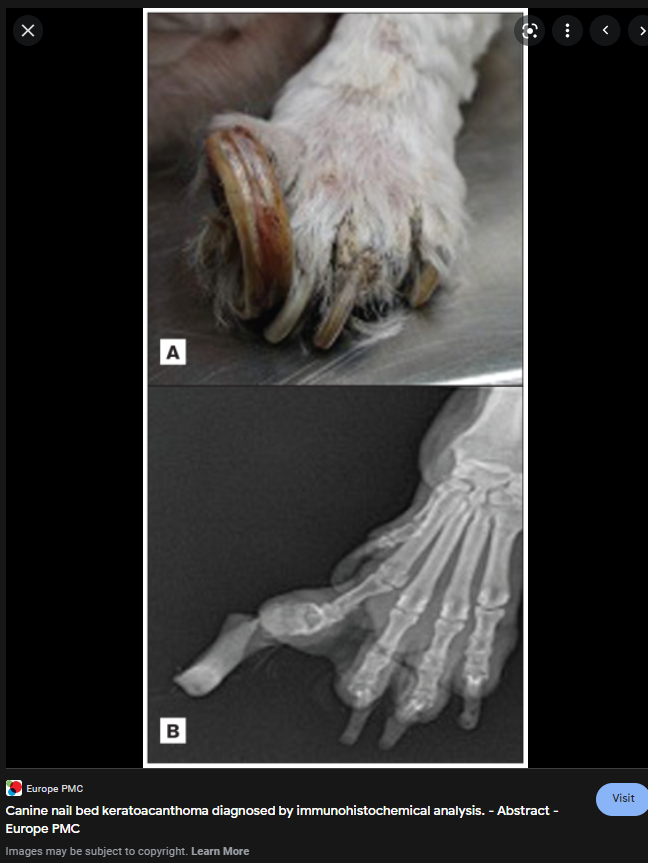

아직 논문이 열리지 않는 최신 지견이라 구글 이미지를 둘러보면

이정도의 영상이 나온다.

이 종양 자체가 양성 종양임에도 불구하고 골 융해를 동반하기 때문에 기능적인 부분에서는 악성형의 증상을 보인다고 할 수 있을 듯 하며

squamous cell calcinoma , synovial cell sarcoma, osteosarcoma와 감별이 필요한 질환이기도 함